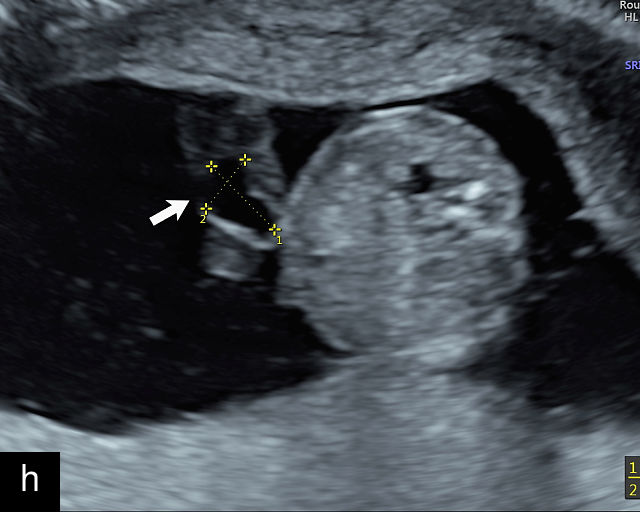

21

(a) Type-1 vasa previa. Photograph after delivery showing the umbilical cord inserting into the membranes through which unprotected fetal vessels run to insert into the placental edge. (b) Type-2 vasa previa. Photograph after delivery showing bilobed placenta with unprotected fetal vessels running though the membranes between the lobes. (c) Type-3 vasa previa in a twin pregnancy. Photograph after delivery showing unprotected vessels running through the membranes from one edge of the placenta to another (arrow). (d) Transabdominal grayscale ultrasound of the lower uterine segment showing a linear hypoechoic structure (fetal vessel) running over the cervix (c) indicating vasa previa (Type 2). b, bladder; h, fetal head. (e) Transabdominal color Doppler ultrasound of the lower uterine segment showing fetal vessels (arrow) running over the cervix (c) indicating vasa previa (Type 2). (f) Transabdominal ultrasound with color flow and pulsed-wave Doppler of the lower uterine segment showing a fetal vessel running over the cervix (c) indicating vasa previa (Type 2). Pulsed-wave Doppler demonstrates an umbilical arterial waveform. (g) Transvaginal grayscale ultrasound with showing a Type-2 vasa previa. There are two placental lobes, an anterior (a) and a posterior (p) lobe. There is a linear and circular hypoechoic structure (arrow) running over the cervix (c) between the lobes. (h) Transvaginal grayscale ultrasound image of vasa previa. A hypoechoic linear structure (arrow) is seen running through the membranes over the cervix (c). h, fetal head. (i) Transvaginal grayscale ultrasound of vasa previa. Hypoechoic circular and linear structures are seen close to the internal os. (j) Transvaginal color Doppler ultrasound image of vasa previa. A fetal vessel is seen running through the membranes over the internal os (arrow) of the cervix (c). h, fetal head. (k) Transvaginal ultrasound with color Doppler showing a Type-2 vasa previa. There are two placental lobes, an anterior and posterior lobe (pl). Fetal vessels run over the cervix between the lobes. (l) Transvaginal color flow ultrasound with pulsed-wave Doppler image of vasa previa. Color Doppler shows flow through the vessel and pulsed-wave Doppler shows a fetal umbilical venous waveform. (m) Transvaginal color ultrasound with pulsed-wave Doppler image of vasa previa. Color flow Doppler shows flow through the vessel and pulsed-wave Doppler shows a fetal umbilical arterial waveform. (n) Transvaginal three-dimensional ultrasound with color Doppler image of vasa previa. h, fetal head; c, cervix.

12